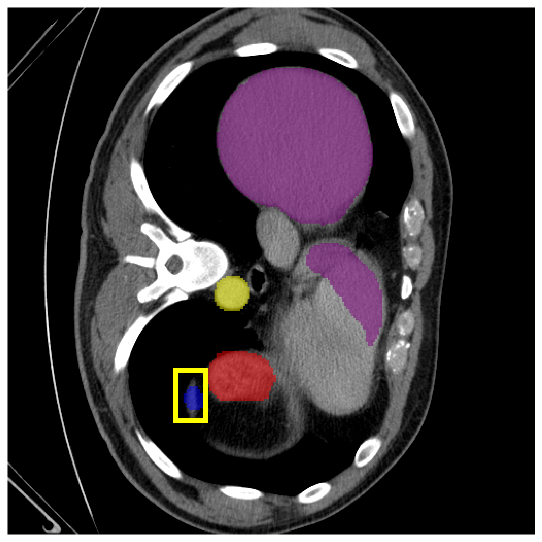

4.3.2 Visual Comparisons

Visualization of our method on the Synapse and ACDC datasets is shown in Fig. 3(a) and Fig. 3(b). For the Synapse dataset illustrated in Fig. 3(a), FCT failed to accurately segment SM and GB, while MERIT achieved precise segmentation of SM but struggled with GB. In contrast, our method achieved accurate segmentation of both SM and GB. Regarding the ACDC dataset shown in Fig. 3(b), while previous methods achieve comparable segmentation of the Myo and LV to the GT, they exhibit noticeable errors on the RV, including invasion into adjacent organs and misrecognition. On the other hand, our method accurately segments across all three structures Myo, LV, and RV, performing as precisely as the GT. We demonstrate the superiority of our method quantitatively and qualitatively.